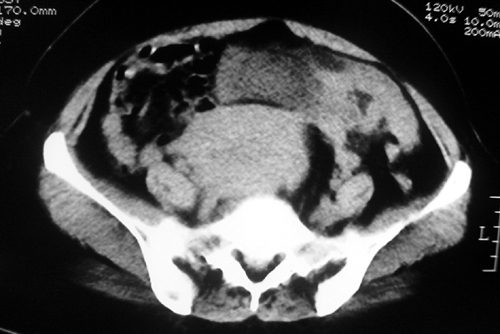

以下是引用余辉在2009-2-14 8:37:00的发言:[br]宫颈左后壁见较大低密度肿物影且向左后上方突出,宫腔内见大片状低密度区,考虑宫颈肿瘤,宫颈癌可能性大,伴宫腔积液或转移